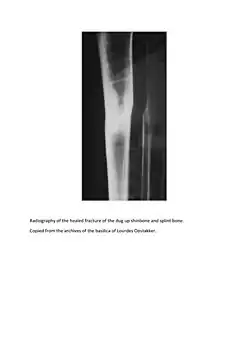

Pieter De Rudder (July 2, 1822 in Jabbeke – March 22, 1898), in many French books Pierre De Rudder, in English Peter De Rudder,[1] was a man whose recovery from a broken leg is one of the most famous recognized Lourdes miracles (a bronze cast of his bones is exhibited in the Lourdes Medical Bureau[2]), although it is not supposed to have occurred in Lourdes itself, but in a sanctuary of Our Lady of Lourdes at Oostakker near Ghent (Belgium, East Flanders).

De Rudder was working for the Viscount Albéric du Bus de Gisignies when on February 16, 1867, in Jabbeke (West Flanders), a falling tree broke the two bones (tibia and fibula) of his left leg.[3]